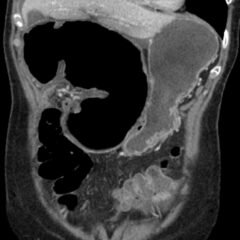

A Case Report of Ogilvie’s Syndrome in a 58-year-old Quadriplegic

Ogilvie’s syndrome (acute colonic pseudo-obstruction) is a rare disorder characterized by an acute dilation of the colon measuring greater than 10 centimeters. Common symptoms associated with Ogilvie’s include abdominal distension, abdominal pain, nausea, vomiting, constipation, and diarrhea. This report presents an uncommon case of a quadriplegic presenting to the emergency department with complaints of abdominal distention. Computed tomography and radiographic imaging studies were consistent with Ogilvie’s syndrome. The patient was admitted to the hospital and started on stool softeners and bowel rest with resolution of symptoms.

Ogilvie’s syndrome, quadriplegic, abdominal distension, colonic pseudo-obstruction.